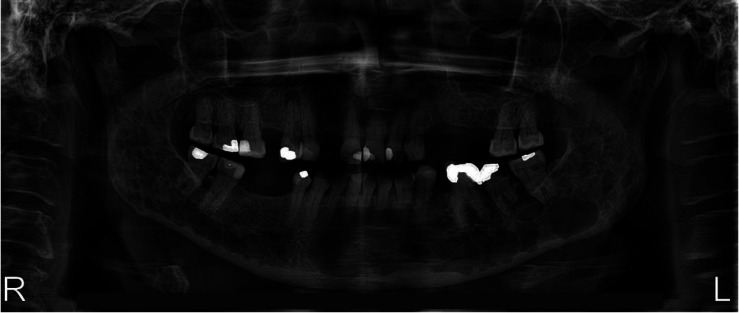

非分泌性多发性骨髓瘤(NSMM)是一种罕见的浆细胞癌症,其特点是血液或尿液中检测不到单克隆M蛋白。一名 57 岁的妇女出现下颌骨疼痛,但无口内肿胀。影像学检查发现她的下颌骨有多处溶骨性病变,左下颌第二磨牙的牙根明显吸收。活检结果显示,非典型浆细胞的抗卡帕抗体、CD138抗体、MUM1抗体和CD79a抗体呈阳性,但抗蓝斑抗体和CD20抗体呈阴性。这些结果表明是恶性浆细胞肿瘤。游离轻链检测、血清或尿蛋白电泳均未发现异常,因此诊断为非小细胞肺癌。患者开始接受化疗和双膦酸盐治疗,治疗后病情得到缓解。本病例强调了牙科医生在早期发现和预防NSMM并发症方面的关键作用,因为这种疾病最初可能出现在口腔中。

Non-secretory multiple myeloma (NSMM) is a rare cancer of plasma cells characterized by the absence of detectable monoclonal M protein in the blood or urine. A 57-year-old woman presented with mandibular pain but without intraoral swelling. Imaging studies revealed multiple osteolytic lesions in her mandible and pronounced root resorption of the left mandibular second molar. Biopsy results showed atypical plasmacytoid cells positive for anti-kappa, CD138, MUM1, and CD79a antibodies, but negative for anti-lambda and CD20. These results were indicative of a malignant plasma cell neoplasm. No abnormalities were revealed by free light chain assay or by serum or urine protein electrophoresis, leading to a diagnosis of NSMM. The patient began chemotherapy in conjunction with bisphosphonate therapy and achieved remission following treatment. This case underscores the critical role of dentists in the early detection and prevention of NSMM complications, as the disease can initially present in the oral cavity.